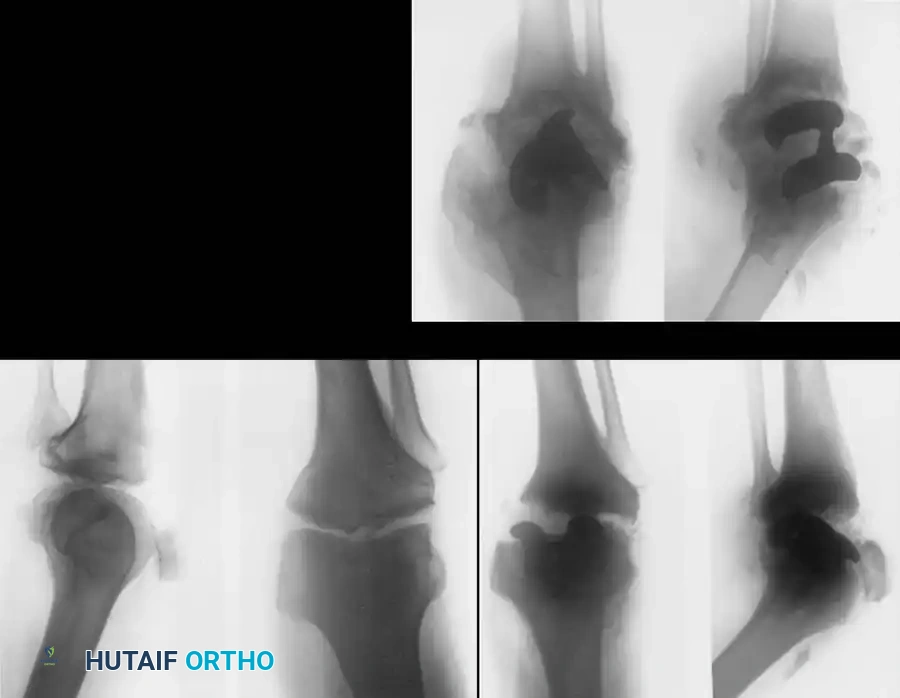

Management of the Neuropathic Knee

If a neuropathic knee is painless and stable, bracing (e.g., a custom knee-ankle-foot orthosis [KAFO]) is the treatment of choice. However, many patients develop disabling instability or pain, necessitating operative consideration.

The Total Knee Arthroplasty (TKA) Controversy:

The use of TKA in neuropathic arthropathy remains highly controversial. The loss of proprioception leads to eccentric loading, rapid polyethylene wear, and massive osteolysis.

While some authors (e.g., Soudry et al., Parvizi et al.) have reported moderate success using highly constrained, hinged, or posterior-stabilized prostheses with custom augments, the complication rates remain unacceptably high. Kim, Kim, and Oh reported that at a 5-year follow-up, only 53% of TKAs in Charcot joints were satisfactory, with frequent catastrophic failures including aseptic loosening, periprosthetic fracture, and complete ligamentous disruption.

Image

Surgical Warning: Total joint arthroplasty in a neuropathic knee is fraught with peril. The lack of protective neuromuscular reflexes inevitably leads to premature implant failure, massive bone loss, and a high likelihood of eventual amputation.

Knee Arthrodesis:

Arthrodesis is universally considered the surgical treatment of choice for the painful, unstable neuropathic knee. Achieving a solid fusion is notoriously difficult due to poor bone stock and impaired healing.

Strict adherence to the following surgical principles is mandatory:

1. Complete Debridement: Meticulous excision of all hypertrophic synovium, necrotic bone, and fibrotic tissue.

2. Careful Carpentry: Precise preparation of apposing bone surfaces (often utilizing cylindrical reaming or flat cuts) to maximize cancellous bone contact.

3. Strong Internal Fixation: Utilization of a long, rigid intramedullary nail spanning from the proximal femur to the distal tibia, or dual orthogonal plating.

4. Adequate External Support: Prolonged postoperative immobilization, often requiring a spica cast or long-leg cast for 6 to 12 months.